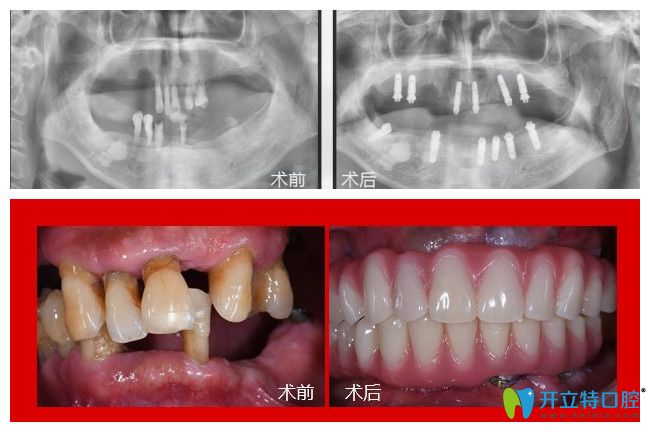

75歲的郭老一年多前在廣州廣大口腔找侯國(guó)鎮(zhèn)醫(yī)生做了all-on-6全口即刻負(fù)重種植牙,不僅效果好而且價(jià)格也不貴,所以考慮再三他決定分享他做全口種植牙的經(jīng)歷及感受。